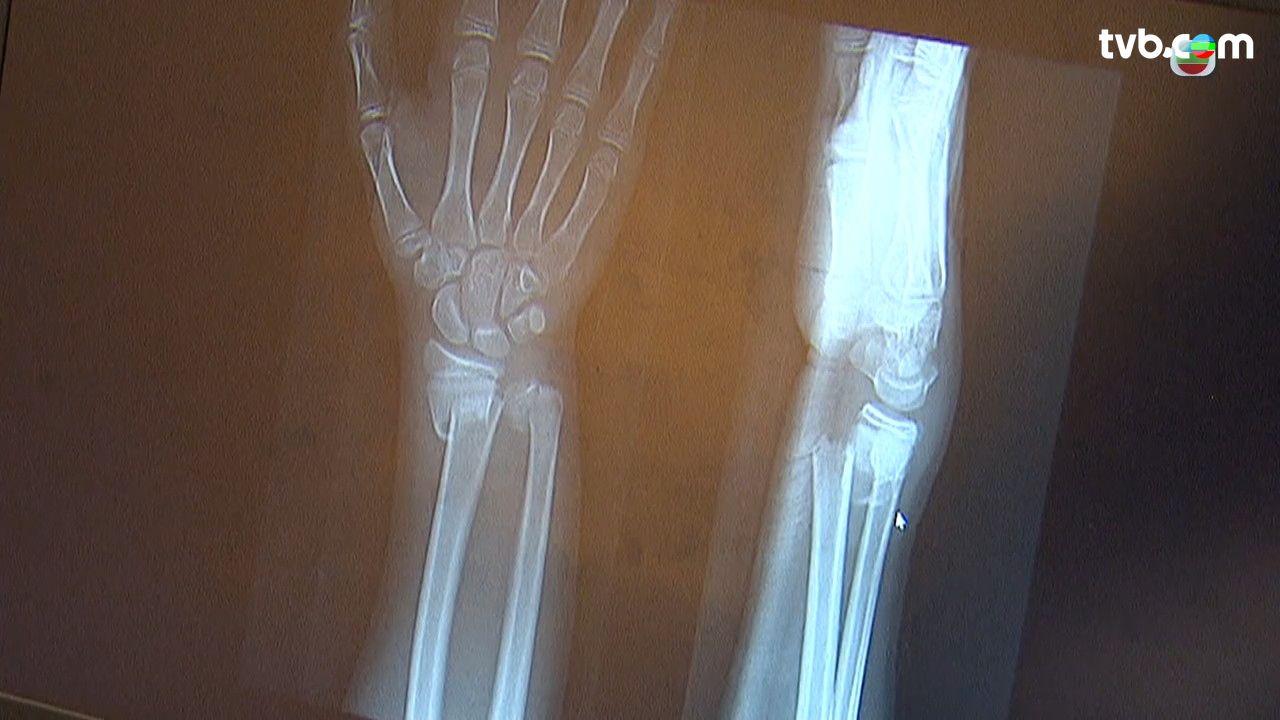

手痛|過度彎曲手腕導致手腕疼痛,有機會是患上了「媽媽手」。《最強生命線》拆解「媽媽手」的成因、治療方法及復原運動。

很多新手媽媽長期手抱嬰兒,容易過度彎曲手腕、拇指外張動作過多及過度用力而患上「媽媽手」。「媽媽手」稱為狹窄性肌腱筋膜炎,筋膜與筋同時發炎,導致筋被筋膜束緊,而形成肌腱筋膜炎。